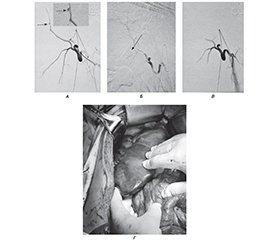

Мета: демонстрація можливостей застосування різних методів зупинки кровотечі з печінки внаслідок вогнепального торакоабдомінального поранення. Матеріали та методи. Пацієнт Х., 25 років, отримав поранення у груди під час мінометного обстрілу, доставлений через годину після поранення до передової хірургічної групи в тяжкому стані, виконаний торакоцентез справа, дренування плевральної порожнини за Бюлау, первинна хірургічна обробка (ПХО) ран. Через 2 години був доставлений до Військово-медичного клінічного центру Північного регіону КМС ЗСУ, госпіталізований до відділення невідкладної медичної допомоги. Встановлено діагноз: поєднане вогнепальне осколкове поранення грудей, живота, кінцівок. Сліпе торакоабдомінальне поранення справа з уламковим переломом VIII ребра, ушкодженням нижньої частки правої легені, правої частки печінки, правої нирки, з наявністю стороннього тіла (металевого осколка) в заочеревинному просторі. Правобічний гемопневмоторакс, пульмоніт. Гемоперитонеум. Сліпе поранення м’яких тканин правого плеча з наявністю стороннього тіла (металевого осколка). Операції: торакоцентез, дренування правої плевральної порожнини за Бюлау. ПХО вогнепальних ран. Пацієнт був оглянутий, виконували лабораторні дослідження: загальноклінічні аналізи крові, сечі, біохімічний аналіз крові, коагулограма крові, група крові та Rh-фактор, тромбоеластографія, електроліти крові, лужно-основний склад та гази крові, ультразвукове дослідження органів грудної клітки (ОГК) та органів черевної порожнини (ОЧП) за FAST-протоколом, мультиспіральна комп’ютерна томографія голови, ОГК та ОЧП і таза з контрастуванням та без контрастування, рентгенографічні дослідження голови, ОГК та ОЧП, електрокардіографія, ангіографічна діагностика та остаточна зупинка кровотечі, видалення стороннього тіла за допомогою інструмента магнітного багатофункціонального для діагностики і видалення металевих феромагнітних сторонніх тіл. Гемостаз рани печінки досягався за допомогою прошивання рани печінки, прийому Прінгла, тампонування серветками, застосування високочастотного електрохірургічного апарата Bowa ARC 303, ізольованого вихідного електрохірургічного генератора Valleylabtm LS10 та Medtronic AEXtm generator Aquamantys. Виконувались оперативні втручання за тактикою damage control surgery. Результати. При надходженні на УЗД грудей та живота за FAST-протоколом: наявна рідина в правій плевральній порожнині та черевній порожнині. При надходженні виконано МСКТ голови, ОГК, ОЧП і таза, виявлено вогнепальний перелом VIIІ ребра справа, посттравматичний пульмоніт нижньої частки правої легені, ознаки ушкодження Sg6, Sg7, Sg8 печінки, марлева серветка в печінці, стороннє тіло (металевий осколок) в ділянці верхнього полюса правої нирки, наявний дренаж у плевральній порожнині, ознаки малого гемопневмотораксу, ознаки гемоперитонеуму. На першу добу через 3 години після поранення виконано операцію DCS I. Лапаротомія, ревізія органів черевної порожнини та позаочеревинного простору справа. Атипова резекція Sg6, Sg7, Sg8 печінки. Ушивання та гемостаз печінки. Ушивання правого купола діафрагми. Видалення стороннього тіла (металевого осколка) за допомогою інструмента магнітного багатофункціонального для діагностики і видалення металевих феромагнітних сторонніх тіл. Тампонування печінки за типом «сендвіч». Ушивання верхнього полюса правої нирки. Санація та дренування черевної порожнини. Закрита лапаростома. Ревізія органів черевної порожнини, гемостаз та ушивання печінки, тампонування печінки за типом «сендвіч», санація та редренування черевної порожнини. Закрита лапаростома. Встановлено діагноз: поєднане вогнепальне осколкове поранення грудей, живота, кінцівок. Сліпе торакоабдомінальне поранення справа з уламковим переломом VIII ребра, ушкодженням нижньої частки правої легені, правої частки печінки (AAST IV), правої нирки (AAST III), з наявністю стороннього тіла (металевого осколка) в заочеревинному просторі. Правобічний гемопневмоторакс, пульмоніт. Гемоперитонеум. Сліпе поранення м’яких тканин правого плеча з наявністю стороннього тіла (металевого осколка). Операція: торакоцентез, дренування правої плевральної порожнини за Бюлау. ПХО вогнепальних ран. З’явились ознаки внутрішньочеревної кровотечі наступної доби з видаленням крові по дренажу з черевної порожнини. Виконано МСКТ голови, органів грудної клітки, органів черевної порожнини і таза з контрастуванням. За даними МСКТ голови, ОГК та ОЧП, таза з контрастуванням виявлені ознаки екстравазації контрастної речовини в черевну порожнину. Наступної доби у зв’язку з наявністю внутрішньочеревної кровотечі з печінки виконані re-look, ревізія органів черевної порожнини, гемостаз та ретампонування печінки, санація, редренування черевної порожнини, лапаростома. Через 12 годин після re-look рецидив внутрішньочеревної кровотечі. Виконана операція: ревізія органів черевної порожнини, гемостаз та ретампонування печінки, санація, редренування черевної порожнини, лапаростома. Через добу після поранення у зв’язку з рецидивом внутрішньочеревної кровотечі з печінки виконана ендоваскулярна емболізація гілок правої печінкової артерії. Виконана діагностична ангіографія судин печінки, під час якої виявлено джерело кровотечі у вигляді псевдоаневризми з однієї з гілок правої печінкової артерії. Права печінкова артерія відходить від верхньої брижової артерії. Виконана суперселективна катетеризація ушкодженої гілки правої печінкової артерії та її емболізація. Гемостаз досягнутий. Через 2 доби після поранення виконані re-look, ревізія органів черевної порожнини, детампонування печінки, санація, редренування черевної порожнини, закрита лапаростома. Через 4 доби після поранення виконано реторакоцентез зліва, дренування плевральної порожнини за Бюлау у зв’язку зі збільшенням кількості рідини в плевральній порожнині. На 5-ту добу після поранення пацієнт переведений на наступний рівень надання медичної допомоги. Відомо, що надалі на 10-ту добу була виконана атипова ререзекція печінки з закриттям лапаростоми та випискою пацієнта на 21-шу добу з представленням на військово-лікарську комісію і наданням відпустки за станом здоров’я на 30 календарних діб. Висновки. У наведеному клінічному випадку проведення ендоваскулярного гемостазу в комплексному лікуванні вогнепального поранення печінки, ускладненого абдомінальною кровотечею, із застосуванням тактики damage control surgery на фоні анатомічних особливостей відходження правої печінкової артерії показало свою високу ефективність.

Background. The goal is to demonstrate the possibilities of using various methods to stop bleeding from the liver due to a thoracoabdominal gunshot wound. Materials and methods. Male patient aged 25 years was wounded in the chest during mortar shelling. An hour after the wound, he was taken to the advanced surgical group in serious condition, and the right thoracocentesis, drainage of the pleural cavity according to Blau, and primary surgical treatment (PST) of the wounds were performed. After 2 hours, the patient was taken to the Military Medical Clinical Center of the Northern Region of the Military Medical Service of the Armed Forces of Ukraine, and hospitalized in the emergency department. The diagnosis was: combined gunshot shrapnel wound of the chest, abdomen, and extremities. Blind thoracoabdominal wound on the right with a comminuted fracture of the VIII rib, damage to the lower lobe of the right lung, right lobe of the liver, right kidney with the presence of a foreign body (metal fragment) in the retroperitoneal space. Right-sided hemopneumothorax, pneumonitis. Hemoperitoneum. Blind wound of the soft tissues of the right shoulder and the presence of a foreign body (metal fragment). Operations: thoracocentesis, drainage of the right pleural cavity according to Blau. PST of gunshot wounds. The patient was examined, laboratory tests were performed: general clinical blood, urine tests, biochemical blood test, blood coagulogram, blood group and Rh factor, thromboelastography, blood electrolytes, alkaline-base composition and blood gases, ultrasound examination of the chest and abdominal organs according to the FAST protocol, multislice computed tomography (MSCT) of the head, chest, abdominal organs and pelvis with and without contrast, radiographic examinations of the head, chest and abdominal organs, electrocardiography, angiographic diagnosis and final stoppage of bleeding, removal of a foreign body using a multifunctional magnetic instrument for the diagnosis and removal of metallic ferromagnetic foreign bodies. Hemostasis from the liver wound was achieved by suturing the liver wound, Pringle maneuver, tamponade with gauze, using a Bowa ARC 303 high-frequency electrosurgical device, an isolated output electrosurgical generator Valleylab™ LS10, and a Medtronic AEX™ generator Aquamantys. Surgical interventions were performed using the (DCS) technique. Results. Upon admission, chest and abdominal ultrasound using the FAST protocol was done: fluid in the right pleural cavity and abdominal cavity. MSCT of the head, chest, abdominal organs and pelvis was also performed, which revealed a gunshot fracture of the right VIII rib, post-traumatic pneumonitis of the lower lobe of the right lung, signs of damage to Sg6, Sg7, Sg8 of the liver, gauge in the liver, foreign body (metal fragment) in the area of the upper pole of the right kidney, pleural drainage in the pleural cavity, signs of small hemopneumothorax, signs of hemoperitoneum. On the first day, 3 hours after the injury, DCS I was performed. Laparotomy, revision of the abdominal organs and the right extraperitoneal space. Atypical resection of Sg6, Sg7, Sg8 of the liver. Suturing and hemostasis of the liver. Suturing of the right dome of the diaphragm. Removal of a foreign body (metal fragment) using a multifunctional magnetic instrument for the diagnosis and removal of metal ferromagnetic foreign bodies. “Sandwich” liver tamponade. Suturing of the upper pole of the right kidney. Sanitation and drainage of the abdominal cavity. Closed laparostomy. Revision of the abdominal organs, hemostasis and suturing of the liver, “sandwich” liver tamponade, sanitation and re-drainage of the abdominal cavity. Closed laparostomy. The diagnosis was established: combined gunshot shrapnel wound of the chest, abdomen, and extremities. Blind thoracoabdominal wound on the right with a comminuted fracture of the VIII rib, damage to the lower lobe of the right lung, right lobe of the liver (AAST IV), right kidney (AAST III) with the presence of a foreign body (metal fragment) in the retroperitoneal space. Right-sided hemopneumothorax, pneumonitis. Hemoperitoneum. Blind wound of the soft tissues of the right shoulder and the presence of a foreign body (metal fragment). Operation: thoracocentesis, drainage of the right pleural cavity according to Blau. PST of gunshot wounds. Signs of intra-abdominal bleeding appeared the next day with blood being removed from the abdominal cavity through drainage. MSCT of the head, chest, abdominal and pelvic organs with contrast was performed, signs of extravasation of contrast material into the abdominal cavity were detected. The next day, due to the presence of intra-abdominal bleeding from the liver, a re-look, revision of the abdominal organs, hemostasis and re-tamponade of the liver, sanitation, re-drainage of the abdominal cavity, and laparostomy were performed. Twelve hours after a re-look, intra-abdominal bleeding relapsed. The operation was performed: revision of the abdominal organs, hemostasis and re-tamponade of the liver, sanitation, re-drainage of the abdominal cavity, laparostomy. A day after the injury, endovascular embolization of the branches of the right hepatic artery was performed due to recurrence of intra-abdominal bleeding from the liver. Diagnostic angiography of the liver vessels was performed, during which the source of bleeding was identified as a pseudoaneurysm from one of the branches of the right hepatic artery. The right hepatic artery originates from the superior mesenteric artery. Superselective catheterization of the damaged branch of the right hepatic artery and its embolization were performed. Hemostasis was achieved. Two days after the injury, a re-look, revision of the abdominal organs, liver detamponade, sanitation, re-drainage of the abdominal cavity, and a closed laparostomy were performed. Four days after the injury, left re-thoracocentesis and drainage of the pleural cavity according to Blau were conducted due to an increase in the amount of fluid in the pleural cavity. On the fifth day after the injury, the patient was transferred to the next level of medical care. It is known that subsequently, on the 10th day, an atypical liver re-resection was performed with laparostomy closure, and the patient was discharged on the 21st day with presentation to the military medical commission and provision of sick leave for 30 calendar days. Conclusions. The presented clinical case of endovascular hemostasis in the comprehensive treatment of gunshot wounds of the liver complicated by abdominal bleeding using the damage control surgery against the background of anatomical features of the right hepatic artery origin showed its high effectiveness.